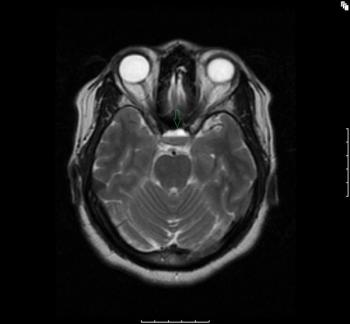

Intermittent blurred vision and palpitations in a young woman often improve after juice. She does not have DM. One day, she arrives at the ED after a seizure. Head CT is negative. What’s next?

Diet and medication can be used to manage symptoms of insulinoma. Once the lesion is well localized, resection is curative.